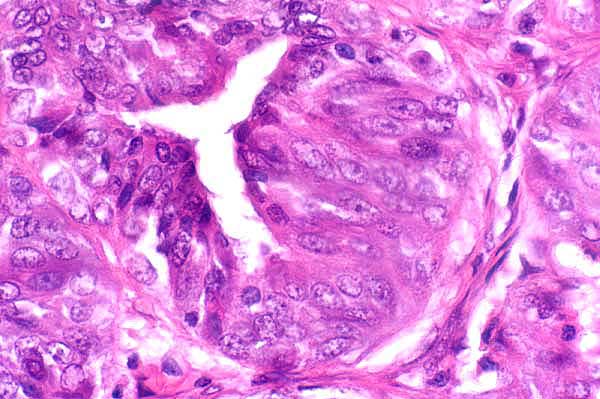

40x   |   Hematoxylin and Eosin

The gland is lined by multiple layers of columnar cells (hyperplasia).